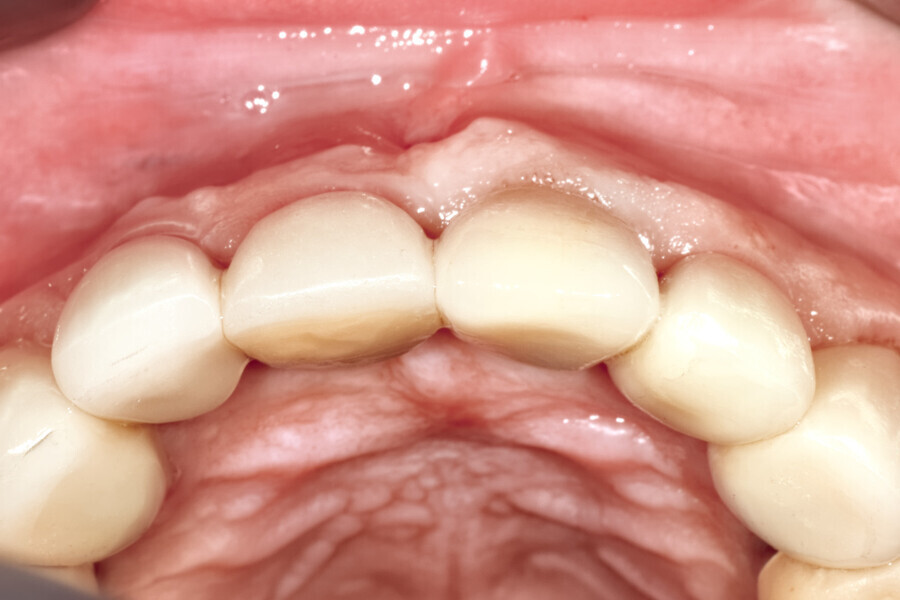

Fig. 12a: A post fracture presenting in the left central incisor, requiring extraction.

Fig. 12b: The occlusal view illustrated the cervical tissue volume and contours.